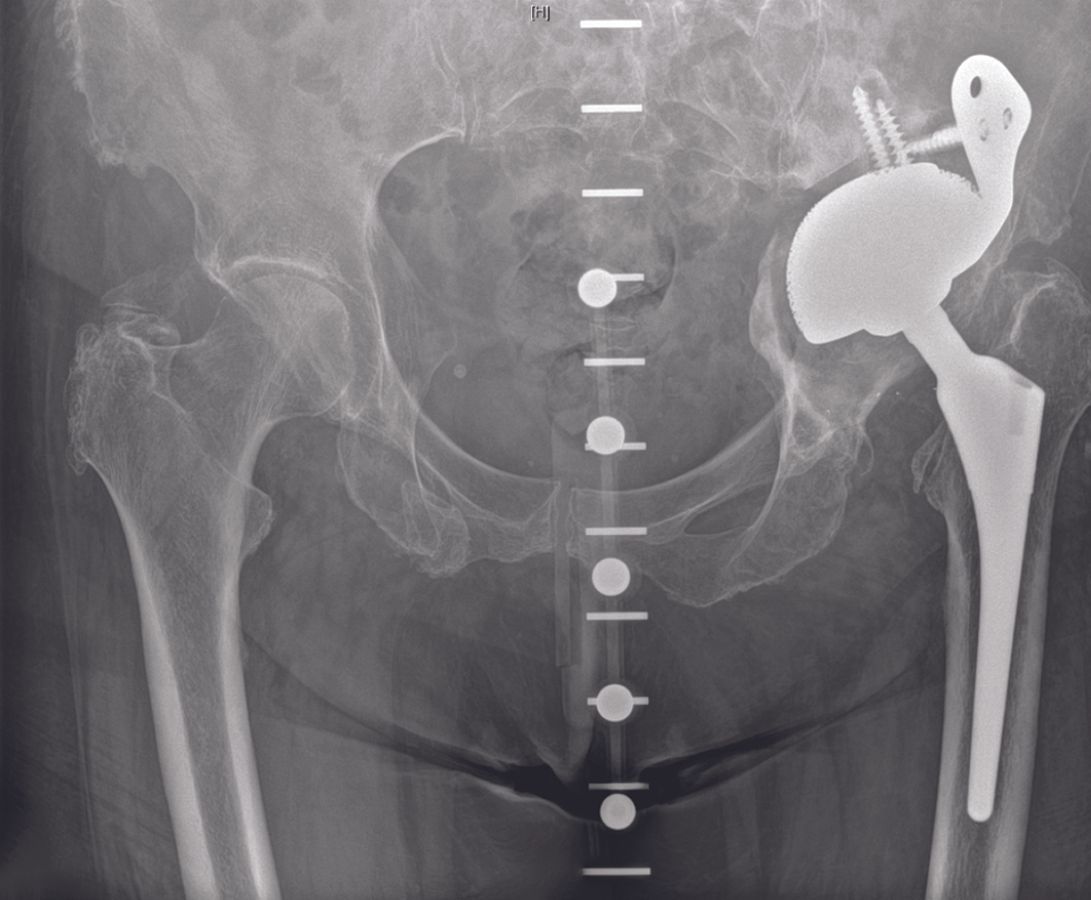

Technique Reconstruction par cage acétabulaire dans les pertes de substance osseuse acétabulaire sévères et les discontinuités pelviennes , Christian Hipfl Centre de chirurgie musculo-squelettique, service d’orthopédie, Charité Universitaetsmedizin Berlin, Charitéplatz 1, 10117 Berlin, Allemagne , Carsten Perka Centre de chirurgie musculo-squelettique, service d’orthopédie, Charité Universitaetsmedizin Berlin, Charitéplatz 1, 10117 Berlin, Allemagne , G.I. Wassilew Service d’orthopédie, Universitaetsmedizin Greifswald, Ferdinand-Sauerbruchstraße, 17475 Greifswald, Allemagne N°291 - Février 2020 ● 13 min de lecture